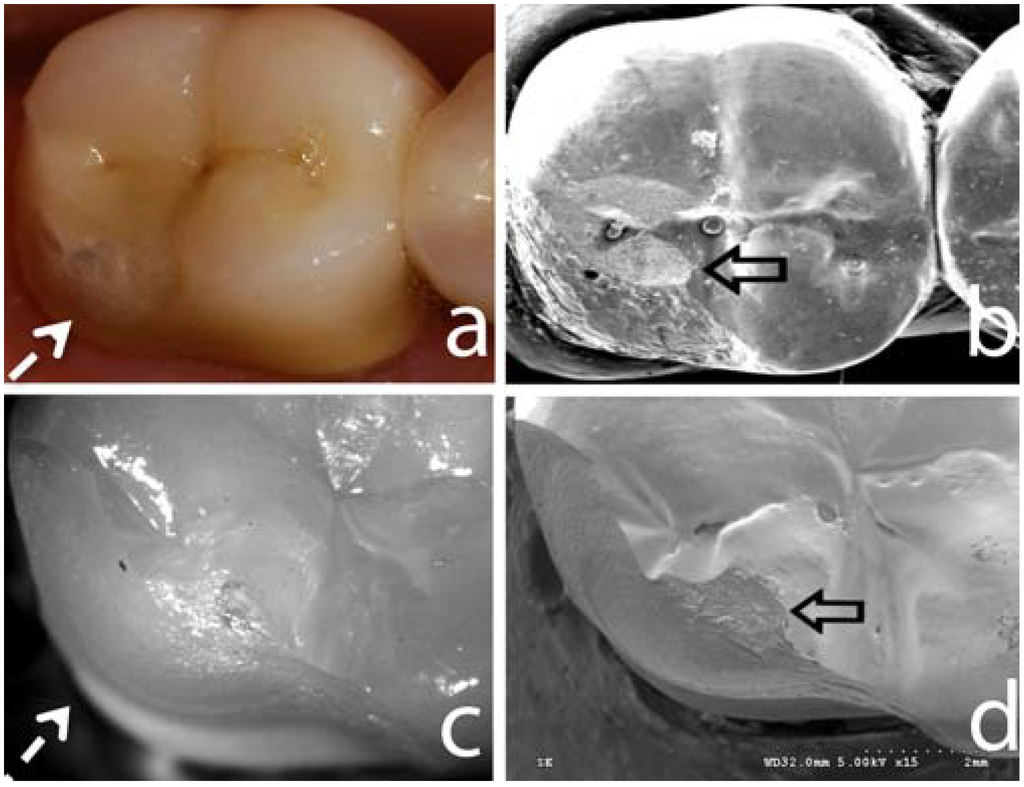

Figure 2.

Image (a) shows a typical clinical fracture (segmented white arrow) of a zirconia-supported all-ceramic restoration after 3 years of service. Image (b) shows a SEM image of the correspondent fracture in (a). Open black arrow points to the rough surface created by occlusal adjustment, supposedly the fracture initiation site. Image (c) is a light polarized picture of fractured specimen obtained using the sliding contact fatigue testing method. Note the similar fracture pattern (d) that this method creates compared to the clinical fracture presented in (a), showing that this methods mimics the in vivo fracture modes. The SEM of the fractured site of the in vivo tested sample (d) is evidenced by the wear facet created by the indenter (open black arrow), similarly what is seen on the SEM image in (b).

Overall, zirconia veneering ceramics are one major concern for the clinical long-term outcome today. The reasons for the problems with the zirconia veneering ceramics still remain to be clarified. Several factors have been investigated in recent laboratory studies, which possibly affect the rate of veneering fractures. Among the factors analyzed are the thermal compatibility of the veneering ceramics and the zirconia frameworks [42,43], different surface treatments of the frameworks [44], the flexural strength of the veneering ceramics [44] and the bond strength between veneering ceramic and zirconia frameworks [44,45,46,47]. Final conclusions on the reasons cannot be drawn up to date. Yet, in the RCT, an interesting clinically relevant observation has been made [48]. It appeared that roughness of the veneering ceramic due to occlusal function or grinding was associated with the chippings (Figure 2). The analysis of the crack propagation direction revealed that the chippings in almost all FDPs had originated from a roughness of the ceramic at the occlusal region of the cusps [48]. This clinical finding is in accordance to recent laboratory investigations using a clinically relevant translational test design (Figure 2) and will be addressed herein as a separated topic. Hence, meticulous polishing of the rough surfaces resulting from grinding or occlusal function is crucial.